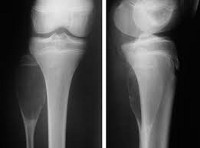

Radiography of limb bones.

Рентген кости. Набор методов радиологического изучения морфологии костно-мышечной системы в нормальных и патологических состояниях. Благодаря высокому содержанию солей кальция и фосфора костная ткань хорошо контрастирует на фоне окружающих мягких тканей. Рентгенологическому исследованию могут быть подвергнуты различные части скелета: кости черепа, грудной клетки, верхних и нижних конечностей, таз. Рентген используется для диагностики переломов костей и контроля их лечения, инфекционных воспалительных процессов, остеопороза, первичных и метастатических опухолей костей, плоскостопия Для большей информативности рентгеновские снимки костей выполняются в двух проекциях, часто с функциональными пробами.

Рентгенография костей. Классический неинвазивный метод диагностики, который позволяет пациентам диагностировать травматические повреждения и заболевания костей быстро, экономично и с минимальным дискомфортом. Это самый старый и самый распространенный метод отображения. Рентгеновские лучи были обнаружены в конце девятнадцатого века немецким ученым Вильгельмом Конрадом. Рентгеновские снимки используются в медицине с 1930-х годов. Он обеспечивает воздействие небольшой дозы ионизирующего излучения на организм человека.

В большинстве случаев для оценки состояния костной ткани рентгенографии костей в двух проекциях достаточно (прямой и боковой). Реже используются три или более проекций. Иногда требуется сравнительная рентгенография костей того же сегмента здоровой конечности. После окончания исследования рентгенолог просит пациента подождать, пока не появятся изображения. Если дополнительные рентгенограммы не требуются, рентгенография костей считается завершенной. Продолжительность процедуры обычно составляет около 10 минут. При использовании контрастного вещества продолжительность рентгенографии костей увеличивается, и до начала исследования лечащий врач вводит контрастное вещество в исследуемую область, а затем рентгенолог делает снимки.